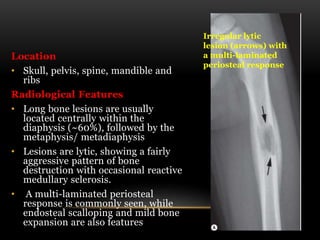

Location

• Skull, pelvis, spine, mandible and

Radiological Features

• Long bone lesions are usually

located centrally within the

diaphysis (~60%), followed by the

metaphysis/ metadiaphysis

• Lesions are lytic, showing a fairly

aggressive pattern of bone

destruction with occasional reactive

medullary sclerosis.

• A multi-laminated periosteal

response is commonly seen, while

endosteal scalloping and mild bone

expansion are also features

Irregular lytic

lesion (arrows) with

a multi-laminated

periosteal response